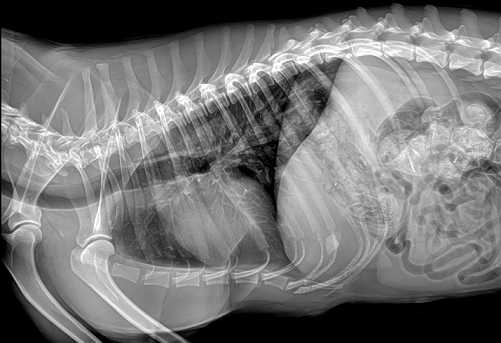

国产品牌普爱医疗宠物DR http://www.pl999.com/class.php?anclss=1&nclass=412采用非晶硅平板探测器,可以令动物影像成像清晰而快速,基本上5s左右就能使动物影像清楚成像且无拖尾现象,而且分辨率高,极限空间分辨率可达到5.0Lp/mm;

普爱医疗拥有雄厚的研发实力,专注于动物影像设备制造,生产的宠物DR图像wsjzodgtl层次丰富,效果细腻清晰,尤其是在极低剂量的情况下的透视还能达到其他厂家宠物DR普通剂量下的效果,以专业的研发实力成为了该行业的佼佼者。想了解产品具体参数及价格信息等,欢迎留言或致电400-6656-888